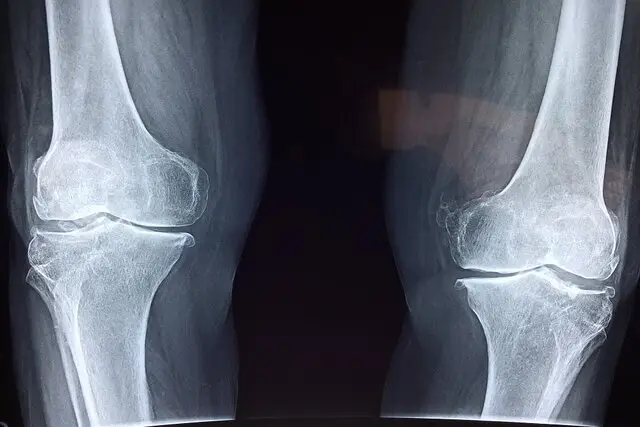

نخستین نگرانی، تاثیر منفی بر سلامت استخوان‌هاست. مصرف نوشابه و الکل هر دو با کاهش تراکم مواد معدنی استخوان و افزایش خطر شکستگی مرتبط است. مصرف نوشابه به‌دلیل وجود اسید فسفریک می‌تواند تعادل کلسیم و فسفر را بر هم بزند و خطر شکستگی لگن را افزایش دهد. مصرف الکل نیز با کمبود کلسیم، اختلال‌های کبدی و کاهش ویتامین دی همراه است که همگی به تضعیف استخوان‌ها منجر می‌شوند.